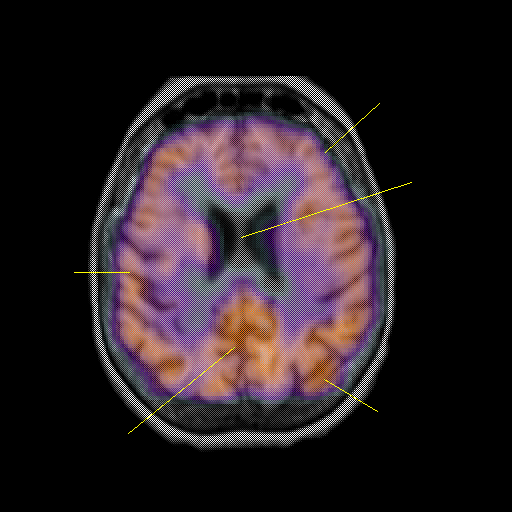

overlay: Slice 35

Slice 35

Unlabeled

Pointers

Labeled